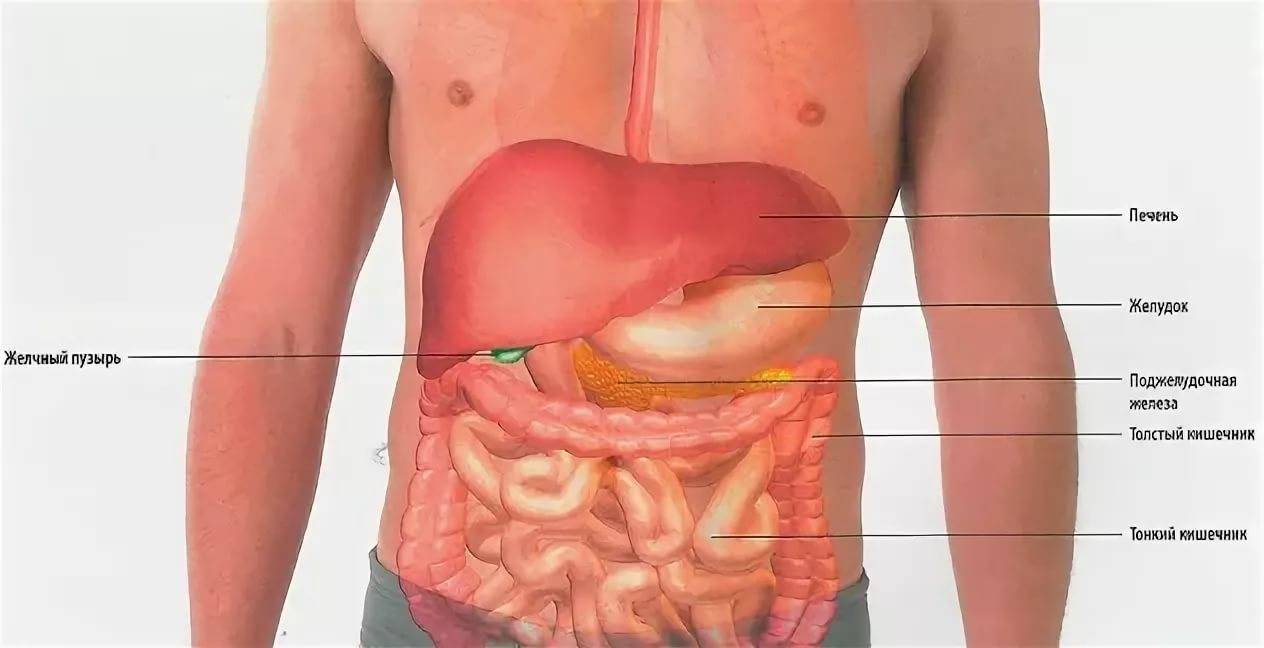

Анатомия желудка и сердца: визуализация и изучение

Раздел: Фотопанорама